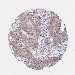

CERVICAL CANCER - Protein expressioni

A mouse-over function shows sample information and annotation data. Click on an image to view it in a full screen mode. Samples can be filtered based on level of antibody staining by selecting one or several of the following categories: high, medium, low and not detected. The assay and annotation is described here.

Note that samples used for immunohistochemistry by the Human Protein Atlas do not correspond to samples in the TCGA dataset.

Antibody stainingi

Antibody staining in the annotated cell types in the current human tissue is reported as not detected, low, medium, or high, based on conventional immunohistochemistry profiling in selected tissues. This score is based on the combination of the staining intensity and fraction of stained cells.

Each image is clickable and will lead to virtual microscopy that enables deeper exploration of all samples and also displays staining intensity scores, fraction scores and subcellular localization as well as patient and tissue information for each sample.

Antibody HPA049074

Antibody HPA054496

Antibody CAB006853

Antibody CAB015948

Staining

High

Medium

Low

Not detected

Intensity

Strong

Moderate

Weak

Negative

Quantity

>75%

75%-25%

<25%

None

Location

Nuclear

Cytoplasmic/membranous

Cytoplasmic/membranous,nuclear

Squamous cell carcinoma, NOS